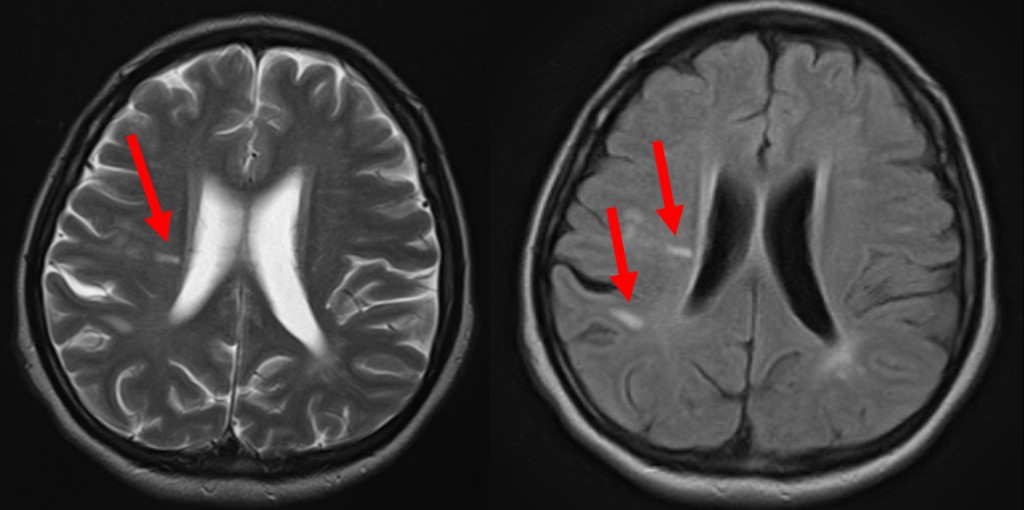

MS は、神経線維を取り囲んで保護する脂肪の鞘であるミエリンに損傷を与えることにより、中枢神経系に影響を与えます。その結果、神経線維自体が変化します。 MS の影響を受けた特定の神経線維は、感覚異常を含むさまざまなMS 症状を引き起こします。